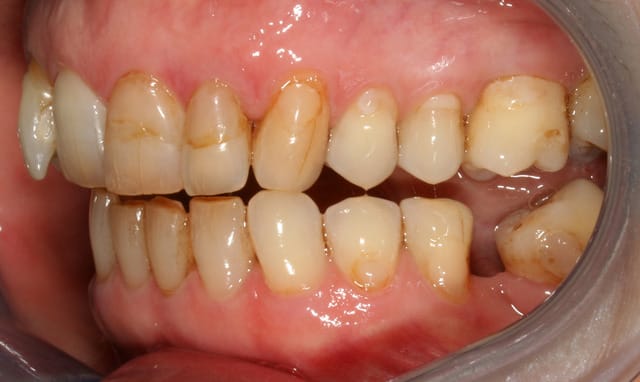

cette patiente que je suis en controle depuis 2 ans, se décide à faire quelque chose pour son sourire.

grosso modo depuis 2 ans, pas de soucis particuliers, pas de caries, faut faire un peu gaffe à la paro mais elle est plutôt motivée et ça se passe bien.

elle a plein de vieux compos d'une mauvaise couleur, au joints colorés, des dents de couleur pas vraiment toutes pareilles ; et un sourire très gingival.

je ne sais pas trop d'ou ça viens, de mylolyses traitées au compo ou d'un épisode de caries au collet ?

elle ne fume pas, bois du thé, un peu de café.